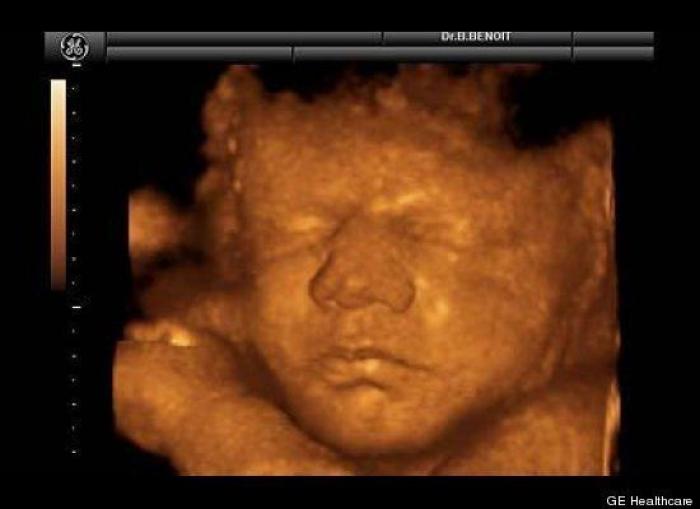

En esta galería puedes ver en fotos como es el desarrollo de un feto de semana en semana:

Desarrollo del feto, en fotos

Ver la galería